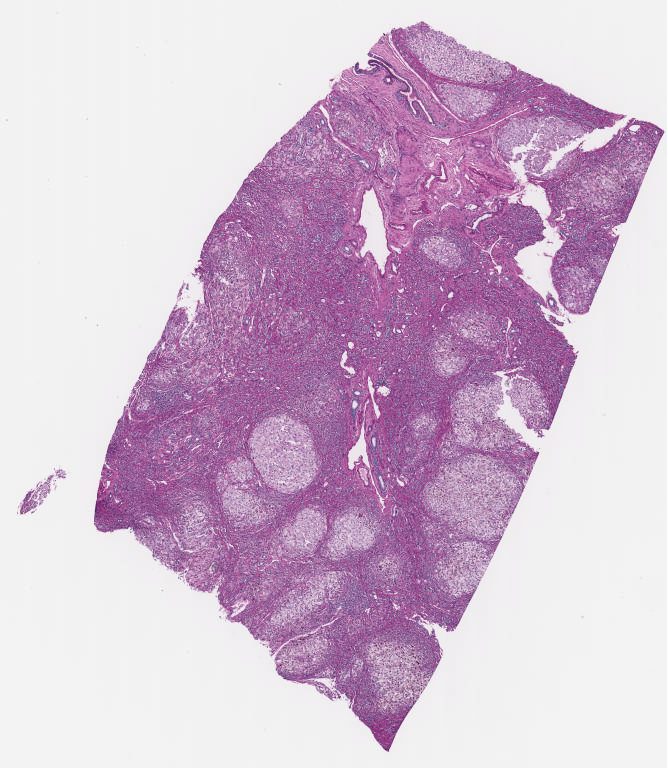

O - Trichrome.svs

34271 x 28944

@ 40X